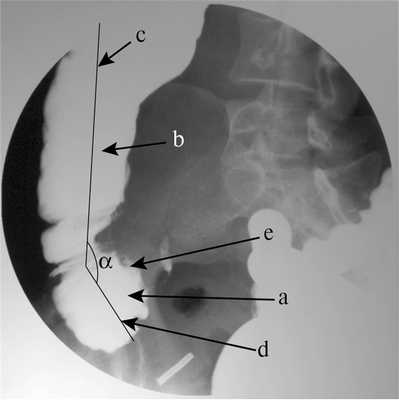

При ирригоскопии выявлена деформация слепой кишки и «изъеденность» ее медиального контура (рис. 2). Рис. 2. Больная Ч., 34 года. Ирригограмма илеоцекального перехода и восходящей ободочной кишки. а — слепая кишка; b — восходящая ободочная кишка; с — ось восходящей ободочной кишки; d — ось слепой кишки; e — изъеденность медиального контура слепой кишки; α — угол между осями восходящей ободочной и слепой кишки. Слепая кишка отклонена медиально, образуя угол 39° по отношению к восходящей ободочной кишке.